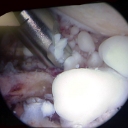

CORSO CHIRURGIA SPALLA

6 Foto

10 anni di

Dott. Luigi Grosso - Ortopedico Traumatologo

Spalla degenerativa

7 Foto